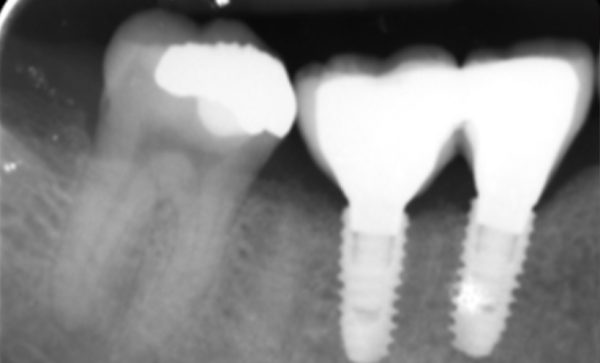

Case 10